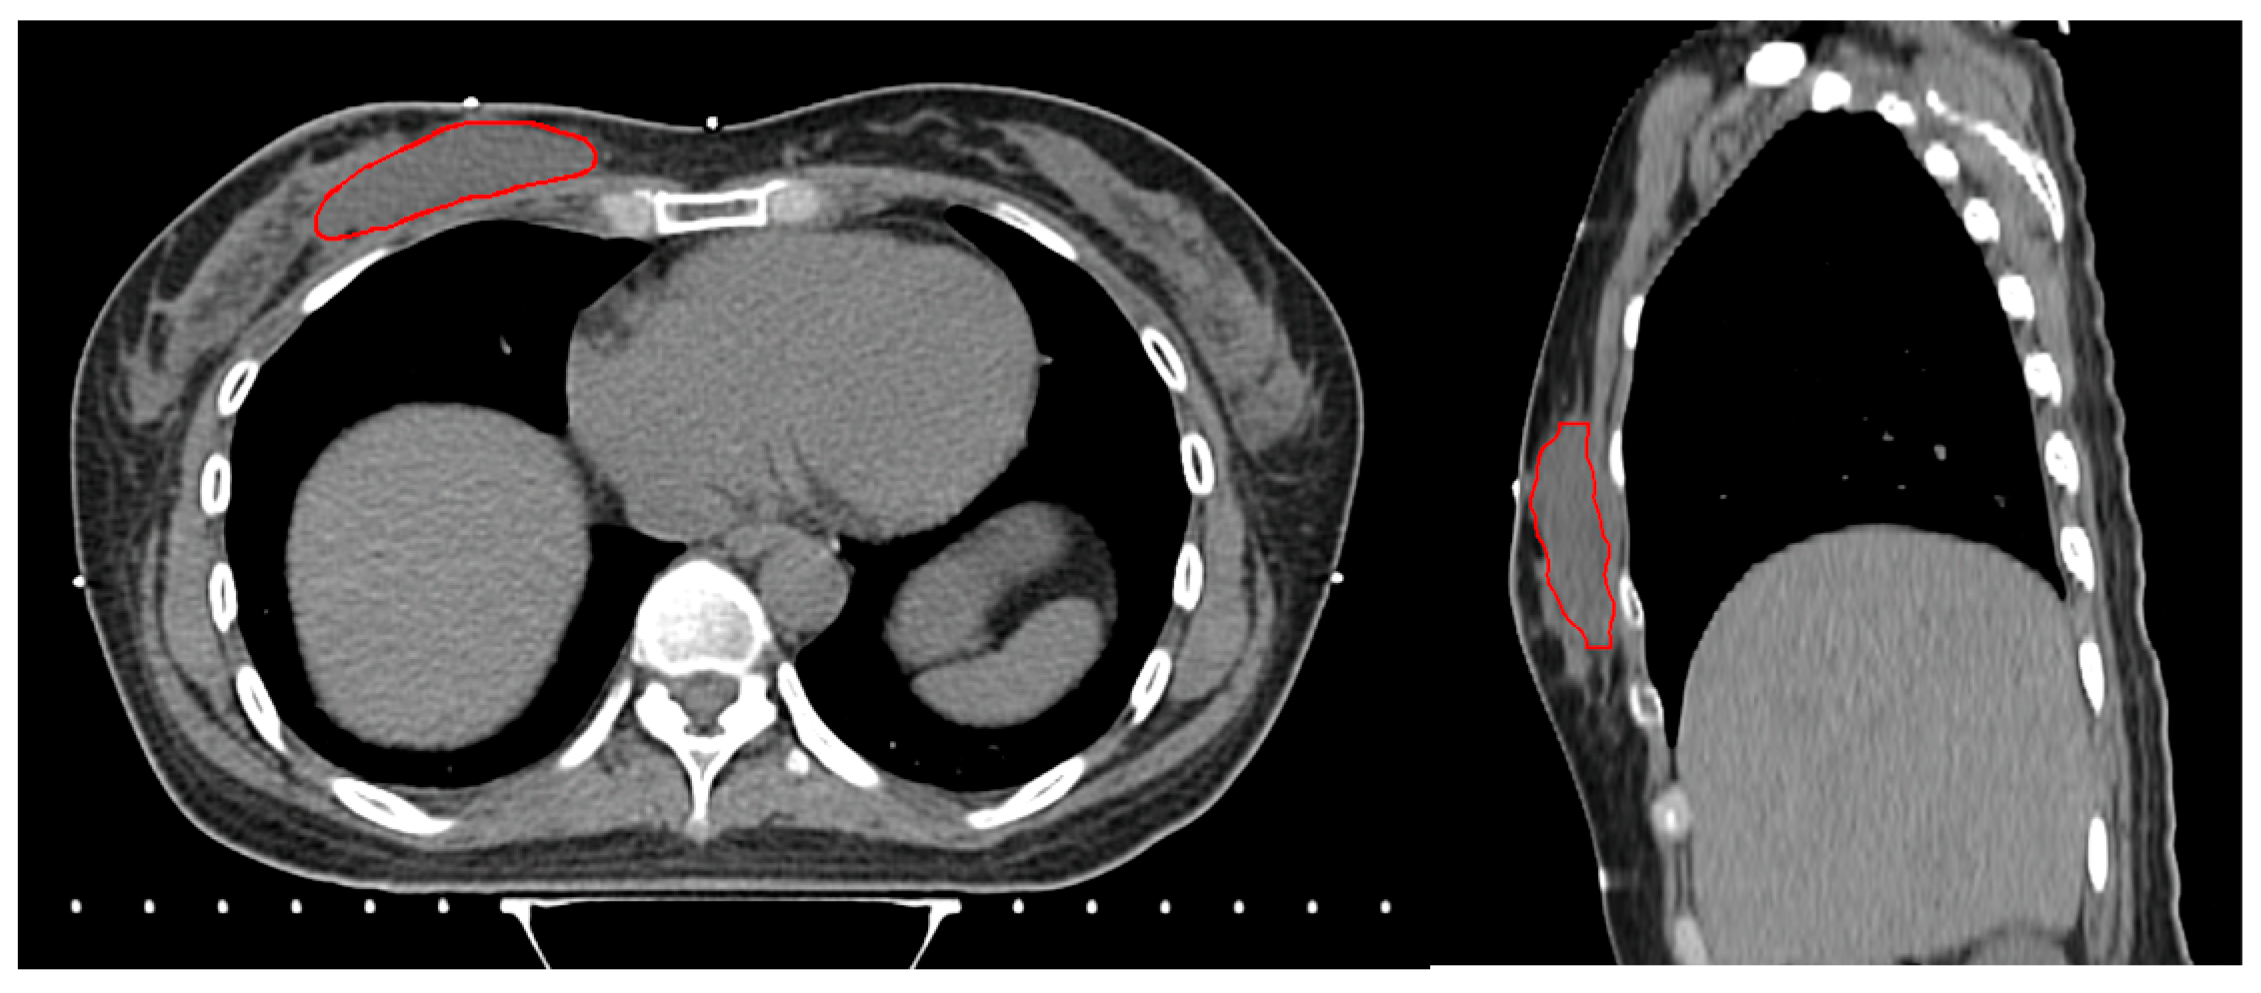

A single radiation oncologist specializing in breast cancer uniformly segmented the volumes (YHL). The cavity-to-breast ratio (%) was calculated as follows (Figure 2):

Cavity-to-breast ratio (%) = (Surgical cavity volume (cc))/(Breast volume (cc)) × 100

Figure 2. Segmentation of whole breast and surgical cavity with large (left) and small (right) cavity-to-breast ratios.